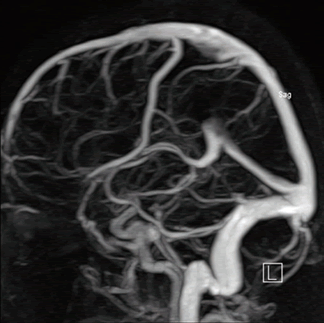

Диагностика магнитно-резонансная ангиография сосудов головного мозга производится при подозрении на тромбофлебит сигмовидного синуса.

Образование тромба является защитной реакцией на проникновение инфекции, но вместе с тем и опасным осложнением тромбофлебита. При маловирулентной инфекции и хороших иммунобиологических реакциях организма тромб может остаться стерильным (известны случаи неожиданного нахождения старого тромба в сигмовидном синусе на МРТ головного мозга (ангиография) и у лиц, умерших от заболеваний, не связанных с ухом). Однако в преобладающем большинстве случаев тромб инфицируется, нередко нагнаивается и сам становится источником инфекции. С током крови инфицированные эмболы или бактерии попадают в малый или большой круг кровообращения.

Тромбоз сигмовидного синуса выявляется при:

- МРТ ангиографии сосудов головного мозга с контрастированием